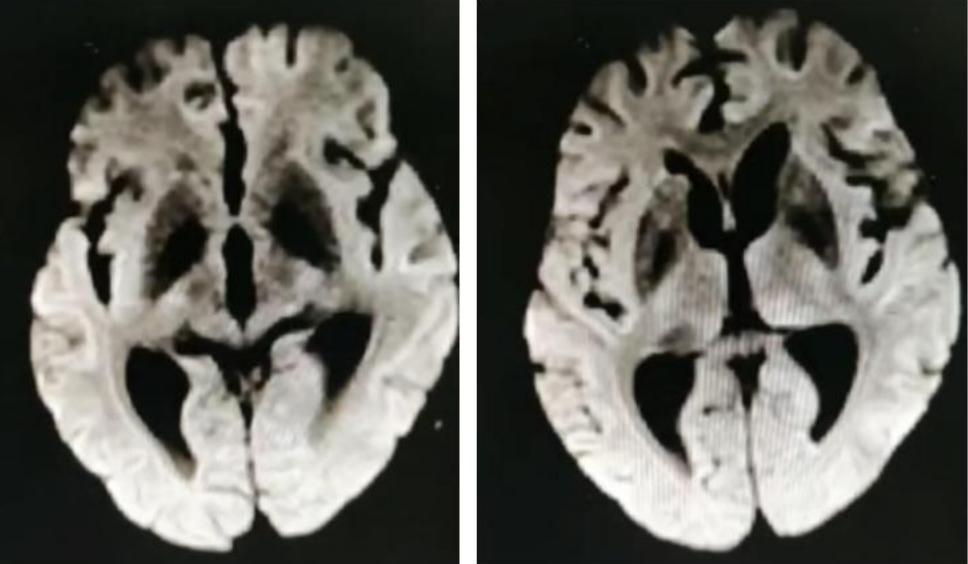

男性50岁,下午睡觉后家属喊不醒,大概4-5小时,之后反应淡漠,右下肢软瘫。

答案:神经梅毒。患者中年男性,急性起病,主要表现为反应迟钝,右下肢软瘫,头颅影像提示以双侧顶枕叶对称性高信号,左侧丘脑点状病灶,额颞叶萎缩。老师们想到了低血糖脑病、PRES、脑梗死、CO中毒等。小僧悟道老师一眼就看出来是梅毒,着实厉害。与年龄不相符的脑萎缩是重要特征。